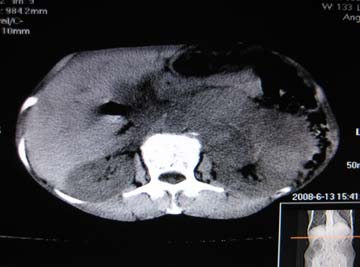

女,65岁,左上腹痛。

肝脏占位  脾脏及胰腺病变   请提供病史

肝脾胃左肾胰都显示不正常啊

病史不详,肝、脾、胰都有占位,谁是原发?

肝脏 脾脏 胰腺都有病变.

胰腺癌伴脾脏侵犯并肝内转移可能性大  建议增强扫描  否则没有确凿的依据

考虑姨尾癌,腹膜后转移\\肝转移

没有病史,没有强化,那就只有猜了,我看病灶很像肝、脾及腹腔多发脓肿,这只是我的意见,

图像欠清,病灶与胃脾胰肾上腺关系显示欠清,建议增强,肝脏考虑转移瘤.

多脏器占位,腹膜后淋巴结增大,淋巴瘤?建议增强扫描